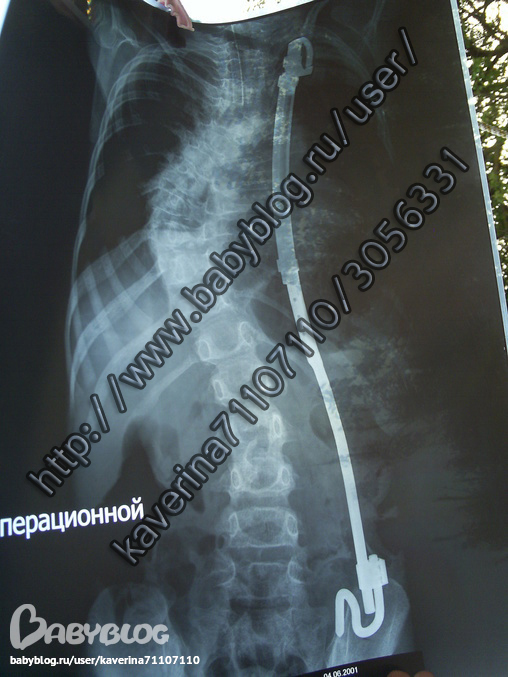

Итак сейчас у нас стоит "растущая" конструкция VEPTR,она немецкая,стоит около 400тыс.руб.Не знаю как сейчас,но на 2009г. такую ставили только в Новосибирском НИИТО. У меня есть официальные отказы из Питера.Институты Альбрехта и Турнера предлагали мне продолжать делать массажи и носить корсеты лет до 14ти.Ребенок в восемь лет был буквой зю,фоток нет к сожалению,не могла смотреть даже,не то что фотографировать(((((((( К 14 годам он мог просто умереть,т.к. внутренности сдавливало сильней и сильней,особенно легкие и сердце. Славик был 28й ребенок в России которому сделали эту операцию.выглядит это так

Внизу конструкция закреплена за тазовую кость,в верху за ребро.За три с лишним года ношения этого чуда-целых ребер (верхних) у ребенка не осталось вообще,т.е после операции-эта штука как-бы натягивает позвоночник. Выравнивает его здорово.А потом,по мере роста-кости не выдерживают,ребро ломается и она болтается просто внутри(((((((((((Четыре раза нам оперативно(под общим наркозом) ее подтягивали,каждые 8-9 мес.Крайний раз наш хирург уже сам стонал и говорил-не знаю за что цеплять. Но мы дотянули до 11,5 лет.И это удача.Внутренности расправились,он стал гораздо меньше болеть)))Т.е. это все было своего рода поддержанием организма.